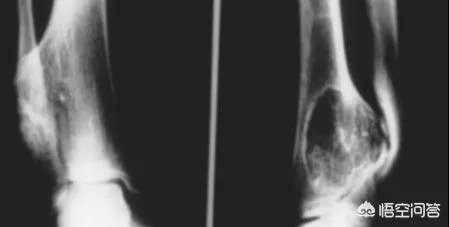

之后到医院去做X光检查,脚部扭伤一般不会骨折,常见的是软组织损伤和韧带拉伤,拍片子是为了排除骨折或者关节错位。如果没有骨折和关节错位,就可以进行下一个步骤的治疗。

1、一旦出现脚扭伤,如果比较严重,建议要去医院行影像学检查,排除踝关节骨折或者第五跖骨基底部骨折;如果比较轻微,可以在家观察一周,48小时以内采取制动和冷敷,超过48小时可以用一些活血化瘀的药物,改善局部血液循环,如果症状没有好转,还是要及时去医院就诊。

2、脚扭伤恢复,首先应该排除骨折,若仅仅是软组织损伤,可以给予局部保护,看能否走路。如果无法自行走路,可以给予石膏或支具,避免负重,局部冰敷,保持局部的皮肤温度在10℃-15℃之间。